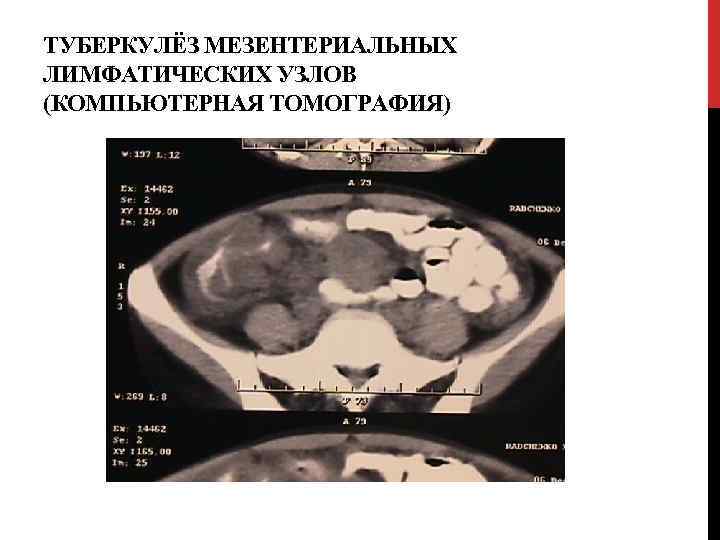

ТУБЕРКУЛЁЗ МЕЗЕНТЕРИАЛЬНЫХ ЛИМФАТИЧЕСКИХ УЗЛОВ (КОМПЬЮТЕРНАЯ ТОМОГРАФИЯ)